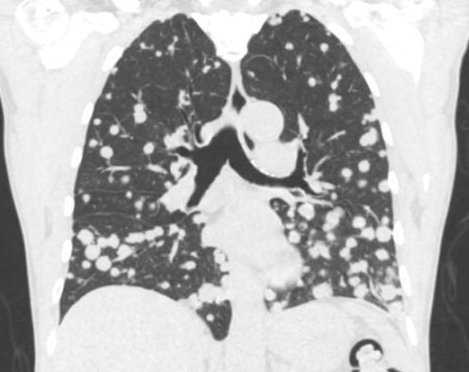

人体恶性肿瘤中有的也称为肉瘤,肉瘤细胞“喜欢”钻入血管,所以,血道转移是肉瘤主要转移途径,如骨肉瘤、横纹肌肉瘤等等。其中主要原因之一是肉瘤中血管十分丰富,而且多数血窦之壁本身就是瘤细胞构成的,因而很易脱落进入血流,出现肺转移。

图3 两边的肺里面象“天女散花”开了癌细胞新花